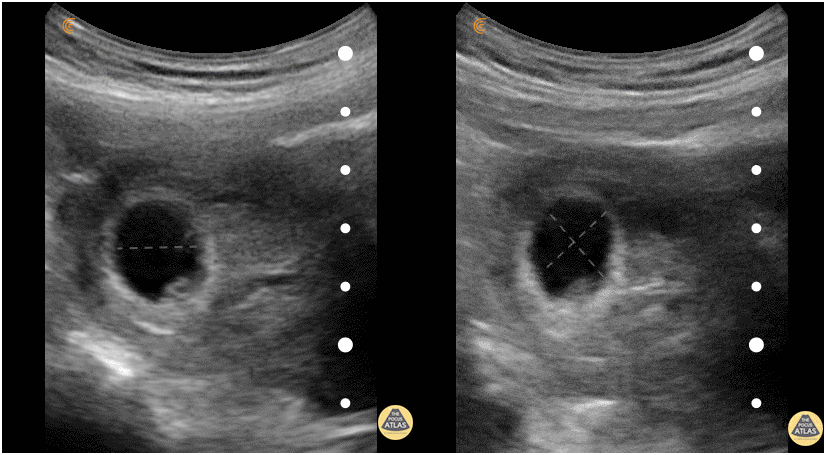

A 28-year-old G0 with an unknown last menstrual period (LMP) presents for a missed period and a positive urine pregnancy (UPT) test two days ago. On abdominal ultrasound, the mean sac diameter is .92 cm consistent with a 4w6d intrauterine pregnancy (IUP). General Rules: MSD is the earliest measurement that can assess GA. MSD can be used until the embryo is present (5w0d-8w0d), then use the CRL. Mean of 3 orthogonal measurements (length, width, and height) of fluid-filled space in sac. Gestational Age (days) = MSD (mm) + 25 This equation can be used when using a portable or handheld device that does not calculate the gestational age automatically. Accuracy3: ± 5-7 days Pearls: A gestational sac alone cannot confirm a pregnancy. In the presence of an ectopic pregnancy, a pseudogestational sac may be present. An MSD > 12.0 cm with no yolk sac visualized should raise concerns for a missed abortion or blighted ovum and should be further investigated.